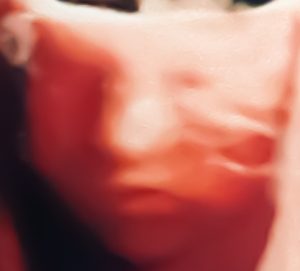

Medicina Fetale:

Ha una grande expertise sul tema della Diagnosi Prenatale, con uno specifico focus sia sugli esami ecografici previsti nelle diverse fasi della gravidanza, che sui test cromosomici e del DNA, che vengono eseguiti in gravidanza, sia essa a rischio o no.

Ecografia Morfologica: 192.00€ 160.00€

Un esame fondamentale che esegue un controllo accurato della struttura di tutta l’anatomia del feto e accerta il numero dei nascituri.